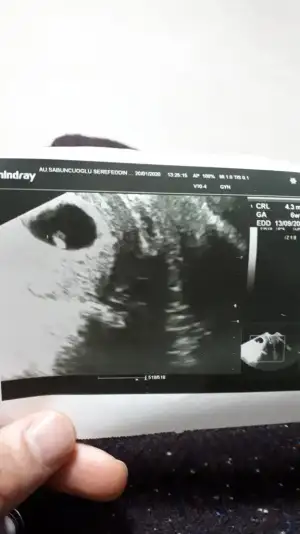

Siz atin bakalim bi ultrason goruntunuzu

canım benim artık keseyi ölçmüyor doktor bebişi ölçüyor bebişte 6.83mm olmuş keseyi ölçmüyor

Kesenin içinde bişi var gibi sanki ama nasıl görüntü aldıysa artık mantıklı ama hiç düşünmedim ben öyle sağolun yasanırım görüntüyü hiç büyütmeden ölçmüş. yanılma payı yüksek olur tabii. ayrıca yolkun da görünmemesi normal bu durumda. büyütüp bakmıştır elbet diye tahmin ediyorum herşeyin normal olduğunu söylediğine göre...

Olcumu pek iyi yapamamis acikcasi . 6.5 cm yaziyor yukarda o da kese boyutu oluyor sanirim

Bebek yokken keseyi bebek varken bebegi olcuyor benimki bu sekilde

6,5 cm kese boyuty değil bence çünkü 5mm dedi kese boyutuna 6.5 cmde bebekte görünmesi lazım büyütme oranı fln mı acaba bilemedimOlcumu pek iyi yapamamis acikcasi . 6.5 cm yaziyor yukarda o da kese boyutu oluyor sanirim

Anladım kuzum bende normalde 7+2 deyim dün doktor bebeği 5mm ölçtü küçük değil mi dedim geç döllenme olmuş olabilir dedi